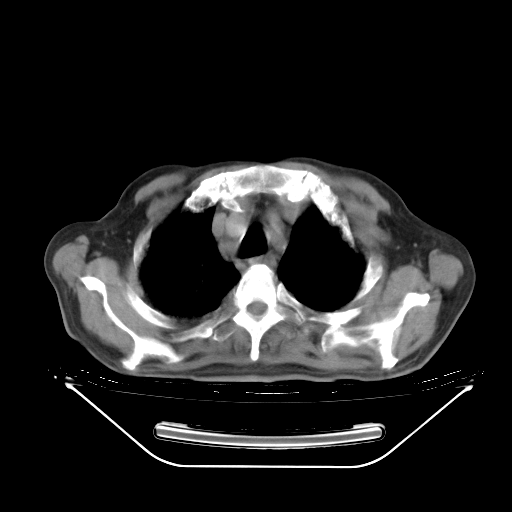

今天复查肺部CT,发现双肺广泛磨玻璃样改变。所以我把3月19日和5月9日相隔50天的肺部CT上传。请大家会诊。

5月9日肺部CT(在4月27日齐鲁医院肺部CT描述部分肺组织磨玻璃样改变,12天后肺组织广泛磨玻璃样改变)

2009年5月9日肺部CT

大致读了系列胸部CT:纵隔窗无明显异常,肺窗:从4、27至今:主要是双肺中下野外带可见毛玻璃样改变,目前处于急性肺泡炎阶段,至于原因考虑1、结替组织或胶原血管性疾病所致?2、恶性疾病如恶组在肺部所致的表现或细支气管肺泡癌?3、药物或其它原因如肺蛋白沉着症所致肺泡炎目前不太可能?总之,明天就去请我院的呼吸科、感染科、血液科和临免专家会诊哈。